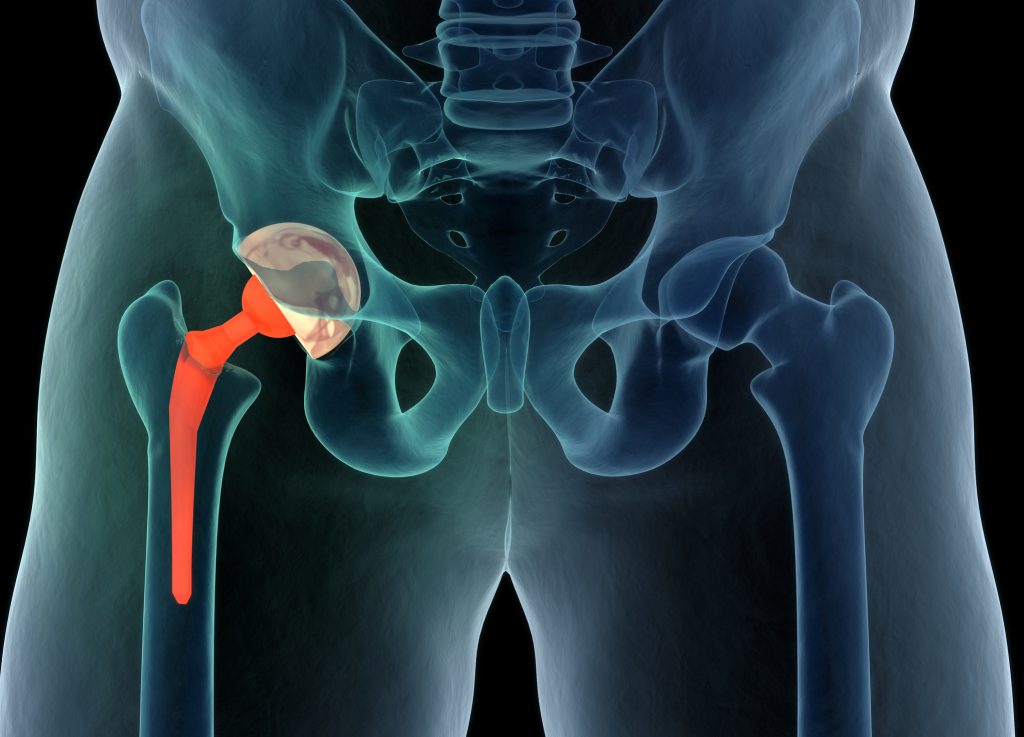

1. خبرة واسعة في جراحة المناظير

- تنظير الركبة

- إصلاح الغضاريف

- إعادة بناء الرباط الصليبي

- تنظير الكتف ومعالجة الخلع

- علاج خشونة المفاصل بالمناظر المتقدمة

🔹 إصابات الركبة

- تمزق الغضروف الهلالي

- إصابات الرباط الصليبي

- احتكاك المفصل

- تنظيف الالتهابات